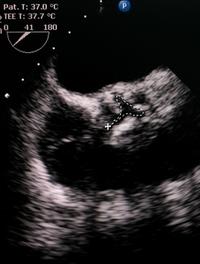

Cardiomyopathie hypertrophique : aujourd’hui et demain

À l’occasion d’une édition spéciale de la revue Journal of Clinical Medicine, Emanuele Monda et coll. ont fait un tour d’horizon des [...]